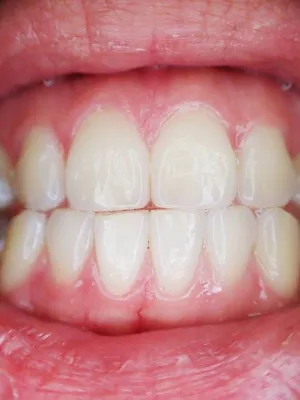

Spécialiste facettes dentaires à Marseille

Facettes dentaires et blanchiment dentaire Marseille

Le Blanchiment dentaire et les facettes dentaires sont des techniques thérapeutiques mise en oeuvre en dentisterie esthétique afin d'améliorer les sourires->Explications et coût.

Facette Dentaire Marseille Prix-Docteur didier TOURROLIER 13005.

Les facettes dentaires -Comment savoir s'y retrouver ? Quels sont les différents types de facettes dentaires ?.Technique de réalisation .A qui confier ce type de traitement?